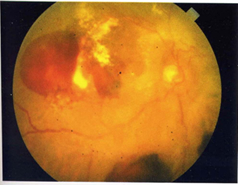

血液が流れていない虚血部に酸素や栄養をなんとか送り込もうと新しい血管(新生血管)が出来る段階です。新生血管は大変もろく出血しやすい血管です。新生血管が破れて網膜の表面や眼球内に出血が広がると、視力に大きな影響を及ぼします。 *障害の状況 増殖網膜症の眼底写真 ・新しい血管が出来る(新生血管) ・新しい血管が破れ、網膜の前方の硝子体に出血が起こる ・増殖膜が出来る ・牽引性網膜剥離が起こる *自覚症状 ・視力の極端な低下 ・黒いものがちらつく ・物がぶれて見える *治療法 ・初期はレーザー光凝固 ・定期的な眼底検査(2〜4週間に1回)

血液が流れていない虚血部に酸素や栄養をなんとか送り込もうと新しい血管(新生血管)が出来る段階です。新生血管は大変もろく出血しやすい血管です。新生血管が破れて網膜の表面や眼球内に出血が広がると、視力に大きな影響を及ぼします。

・新しい血管が出来る(新生血管) ・新しい血管が破れ、網膜の前方の硝子体に出血が起こる ・増殖膜が出来る ・牽引性網膜剥離が起こる

・視力の極端な低下 ・黒いものがちらつく ・物がぶれて見える

・初期はレーザー光凝固 ・定期的な眼底検査(2〜4週間に1回)